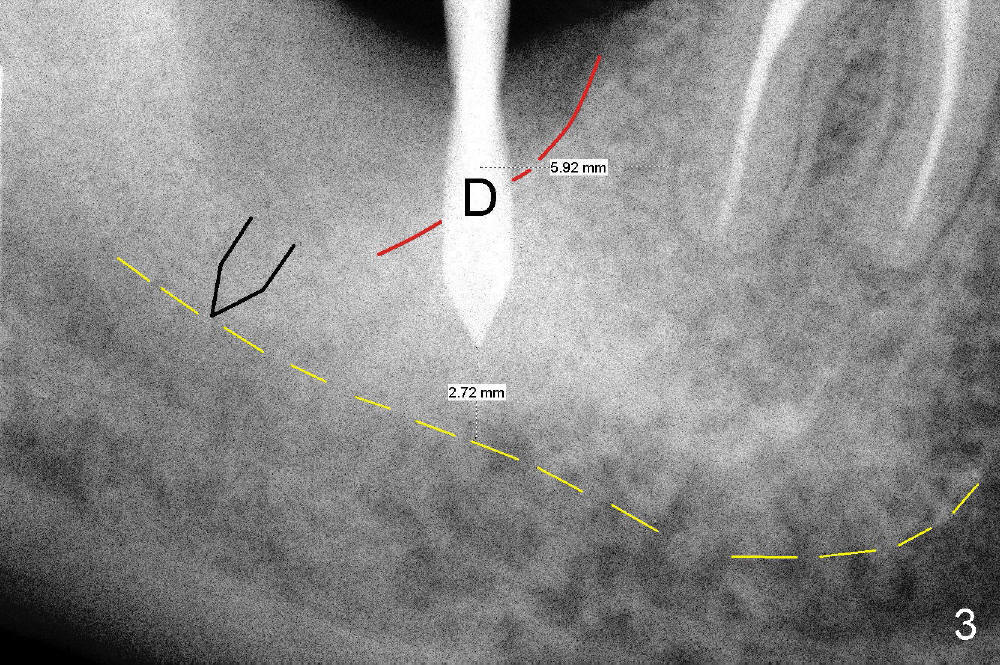

A 62-year-old lady has an advanced endo-perio disease associated with the tooth #31 (Fig.1). IAN is not distinct in the preop PA. IAN is assumed far away from implant area. The implant is planned to be placed along the long axis of the tooth for the best restorative result (Fig.2). The tissue-level implant is placed ~ 3 mm above the distal crest so that implant threads may be less likely exposed postop. Is it a good treatment plan?

No. First at all, CT should be taken when 2D image does not show IAN. Fortunately, the surgery happens to be executed better than the plan. Clindamycin is used for socket soaking for 5 minutes. The initial osteotomy should be not exceeded 6 mm from the distal surface of the first molar (Fig.3: 5.92 mm). The 2 mm pilot drill (D) penetrates the mesial slope of the socket (red line) for 3-4 mm. There is 2.72 mm from IAN (yellow line: upper border of IAN canal). If the implant is placed along the long axis of the tooth, the initial osteotomy should start at the apex of the socket. The same pilot drill (black outline) penetrates the nascent bone for the same distance (3-4 mm) for primary stability, IAN may be invaded! The patient is a severe gagger. She manages to allow us to take this PA (Fig.3) and the next one (Fig.4 with 6x14 mm tap in place, primary stability having been achieved). To close the socket, a 7x14 mm implant is placed. Immediately postop PA is taken twice without success. The socket is closed with 2 sutures and heals around the implant 8 days postop (Fig.5,6). PA is taken 2 months postop (Fig.7). The implant is not placed as deep as planned. It is stable without paresthesia of the lower lip. An abutment is placed (Fig.8: A) nearly 3.5 months postop.